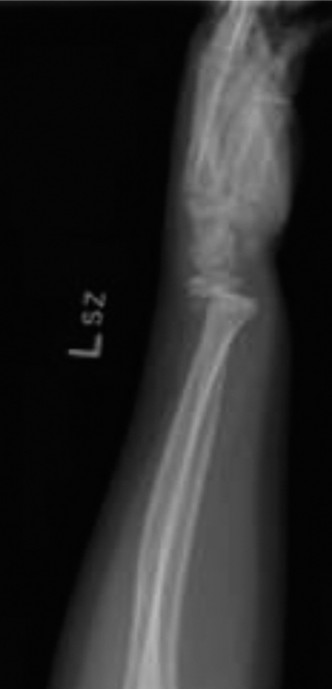

Standard orthopedic trauma radiographic evaluation of the left wrist was obtained, comprising orthogonal posteroanterior, lateral, and oblique projections. Accurate radiographic interpretation requires careful analysis of the fracture geometry, the degree of displacement, and the integrity of adjacent anatomical structures.

The initial posteroanterior projection demonstrated a transverse fracture line propagating through the distal metaphysis of the radius. The fracture line extended proximally from the radial cortex and exited through the physis on the ulnar side.

This specific propagation pattern is the hallmark of a Salter-Harris Type II fracture. There was significant dorsal displacement of the distal epiphyseal-metaphyseal fragment relative to the proximal radial shaft. The lateral radiograph provided critical information regarding the sagittal plane deformity.

The lateral view confirmed the Salter-Harris Type II classification, revealing marked dorsal displacement and an apex volar angulation measuring approximately 35 degrees. Furthermore, there was significant overriding of the fracture fragments, with approximately 75% dorsal cortical translation.

An additional oblique view was obtained to further delineate the metaphyseal component and assess for intra-articular extension or occult carpal pathology.

The oblique projection clearly highlighted the "Thurston Holland fragment." This is the pathognomonic triangular metaphyseal fragment that remains attached to the epiphysis on the compression side of the injury. The presence of this fragment confirms that the fracture line has exited through the metaphysis rather than traversing the entire physis (which would be a Salter-Harris Type I) or entering the epiphysis and joint space (Salter-Harris Type III or IV).

The distal radioulnar joint appeared radiographically congruent on all views, with no evidence of an associated ulnar shaft fracture, ulnar styloid avulsion, or widening of the radioulnar interval. The carpal arcs of Gilula were intact, and the growth plate of the distal ulna appeared uninjured.